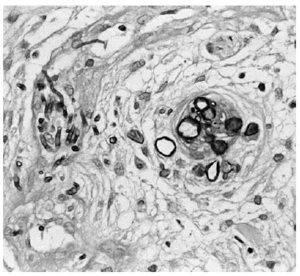

La biopsia de piel mostró discreta espongiosis y exocitosis linfocitaria en la epidermis, observándose en dermis papilar y reticular una intensa infiltración por elementos fúngicos en forma de hifas tabicadas y no tabicadas, en ocasiones bifurcadas, y por estructuras de tipo levaduriforme (fig. 2). Estas hifas tenían afinidad por las paredes vasculares a las que invadían (fig. 3). La respuesta inflamatoria acompañante es prácticamente nula. En el cultivo de la biopsia cutánea se identificó un hongo del género Fusarium, siendo los hemocultivos, cultivos del catéter y de esputo negativos.

Fig. 2.--Intensa infiltración por elementos fúngicos en dermis media y profunda (H&E).